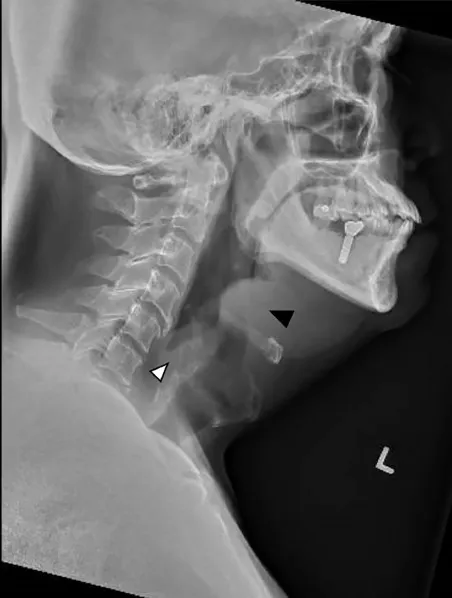

Acute Epiglottitis: Bacterial (H. influenzae, Strep.). X-Ray (Lateral Neck) shows Thumb Sign (swollen epiglottis).

⭐ Exam Favourite: Croup's "Steeple sign" is best seen on an AP view of the neck, whereas the "Thumb sign" of epiglottitis requires a lateral view.